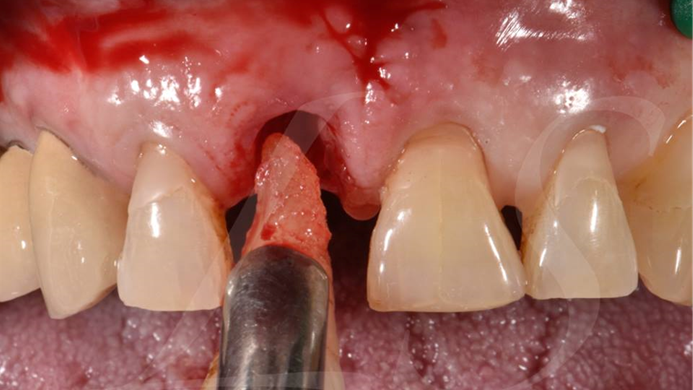

“ One implant /One tooth/ One hour step-by-step

+ associated connective graft ”

Clinical case: EImmediate implant placement & loading of #35 extraction socket with defect

- Courtesy of Dr. Kwang Bum Park, Korea -

Dr. Laurent Sers, immediate loading, digital guided surgery, digital ONE-DAY implant, maxillary anterior, #21, guided surgery, immediate loading, AnyRidge, R2GATE, Mega ISQ, R2GATE Full Surgical Kit

implant system, R2GATE Guide, R2GATE surgical kit (AnyRidge), Mega ISQ